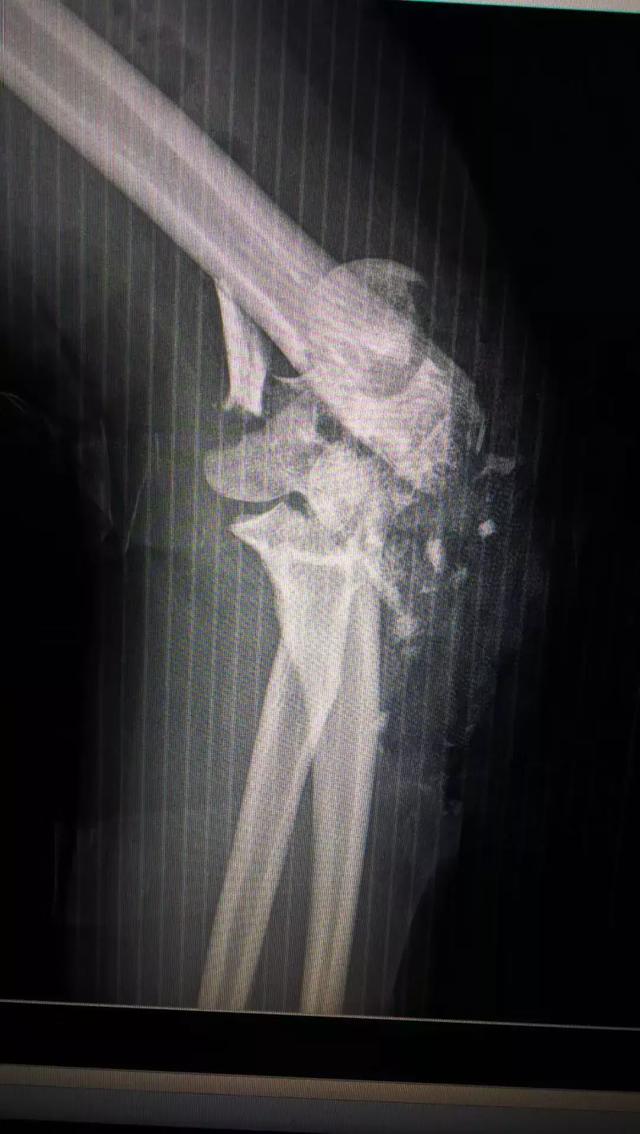

故事发生在去年夏天,高考完的第一天,从急诊科收治来一位年轻女性伤员,左侧肘关节开放性粉碎性骨折合并血管伤,关节接近毁损。虽然张主任对这类伤有较丰富的经验,但当时医院刚开业半年,新的骨科团队面临一些挑战。迫于伤员病情急重,必须立即手术不能耽搁,伤员家属也予以充分的信任。

.术前术后对比图